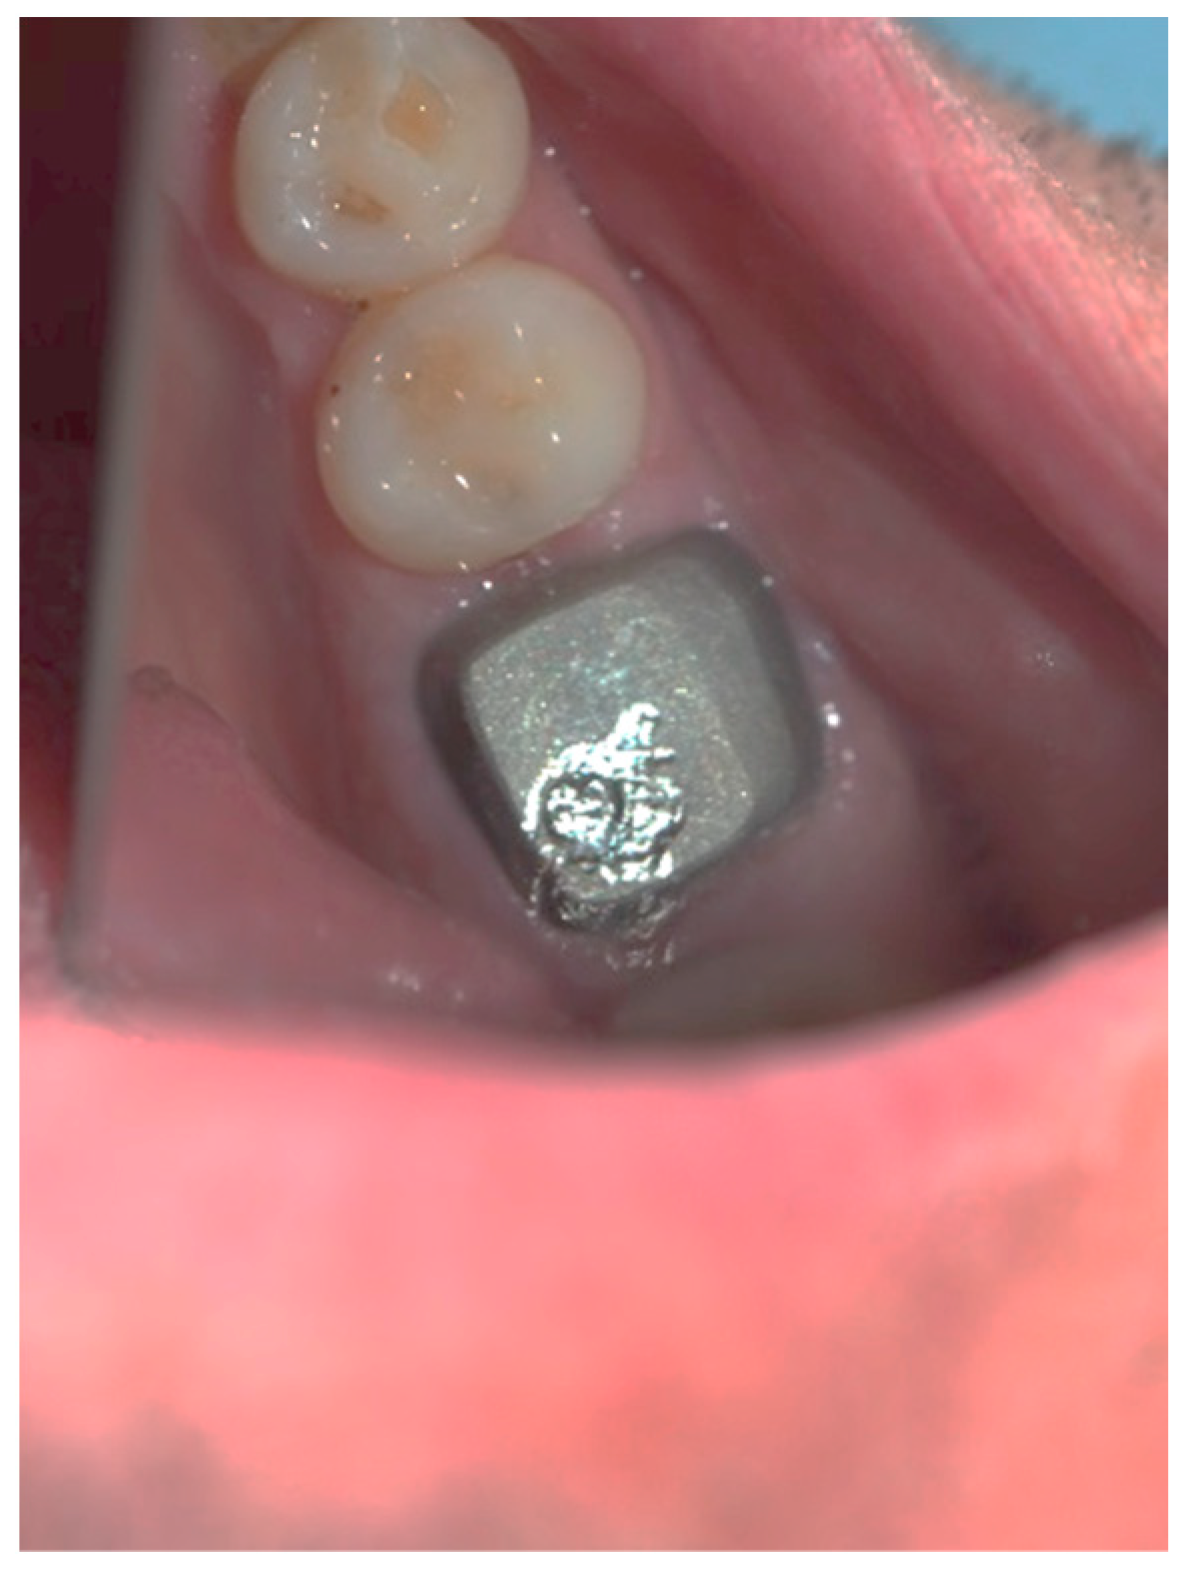

Figure 3, Figure 4, Figure 5, Figure 6, Figure 7 and Figure 8 display the follow-up of the healing process after a resective procedure for lengthening a short clinical crown with a laser.

Figure 3.

Soft tissue lengthening of a short clinical crown and subgingival finish line exposure of tooth 36: bleeding during the procedure was self-limiting, and the post and core impression was taken in the same visit.